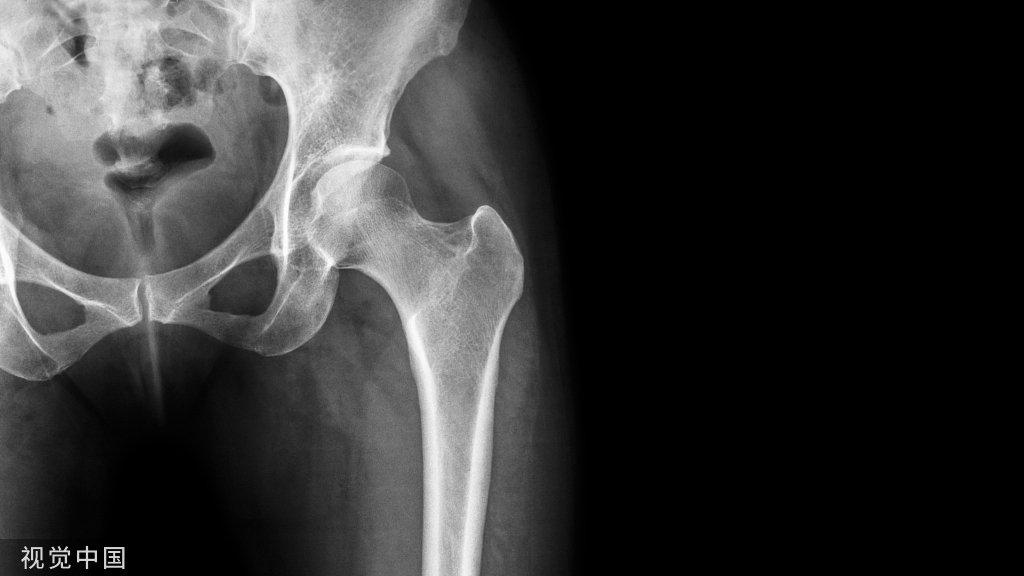

骨质疏松性骨折(脆性骨折) 指受到轻微创伤或日常活动即可发生的骨折,常见部位是椎体、髋部、前臂远端、肱骨近端和小腿远端等。

骨质疏松性骨缺损是指骨质疏松性骨折后骨的结构完整性破坏而发生的缺损。由于骨微结构改变,骨矿成分和骨基质成分沉积不断减少,骨小梁稀疏断裂,骨强度下降,骨脆性增加,骨质疏松性骨折经常伴随骨缺损。